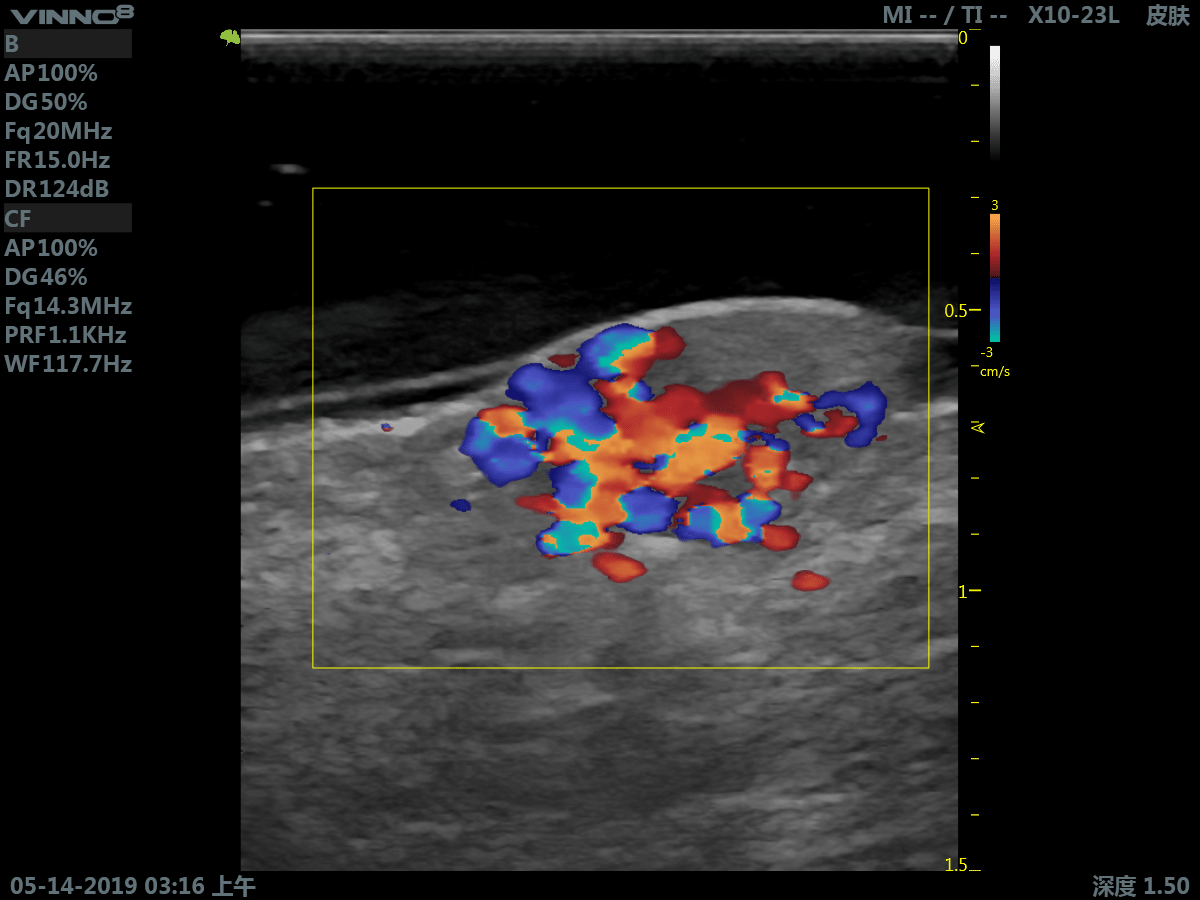

Портативный ультразвуковой сканер VINNO 8

Преимущества портативного УЗИ аппарата VINNO 8

- инновационная платформа RF обеспечивает суперчистое изображение в результате сверхвысокой скорости обработки данных

- широкий выбор датчиков и функций

Клиническое применение:

- мелкие объекты (включая щитовидную железу, молочную железу, семенники и т.д.)

10. CFM. Режим цветового допплера

11. CFM+B (B+CF). Комбинированный режим: цветовое допплеровское картирование + В режим